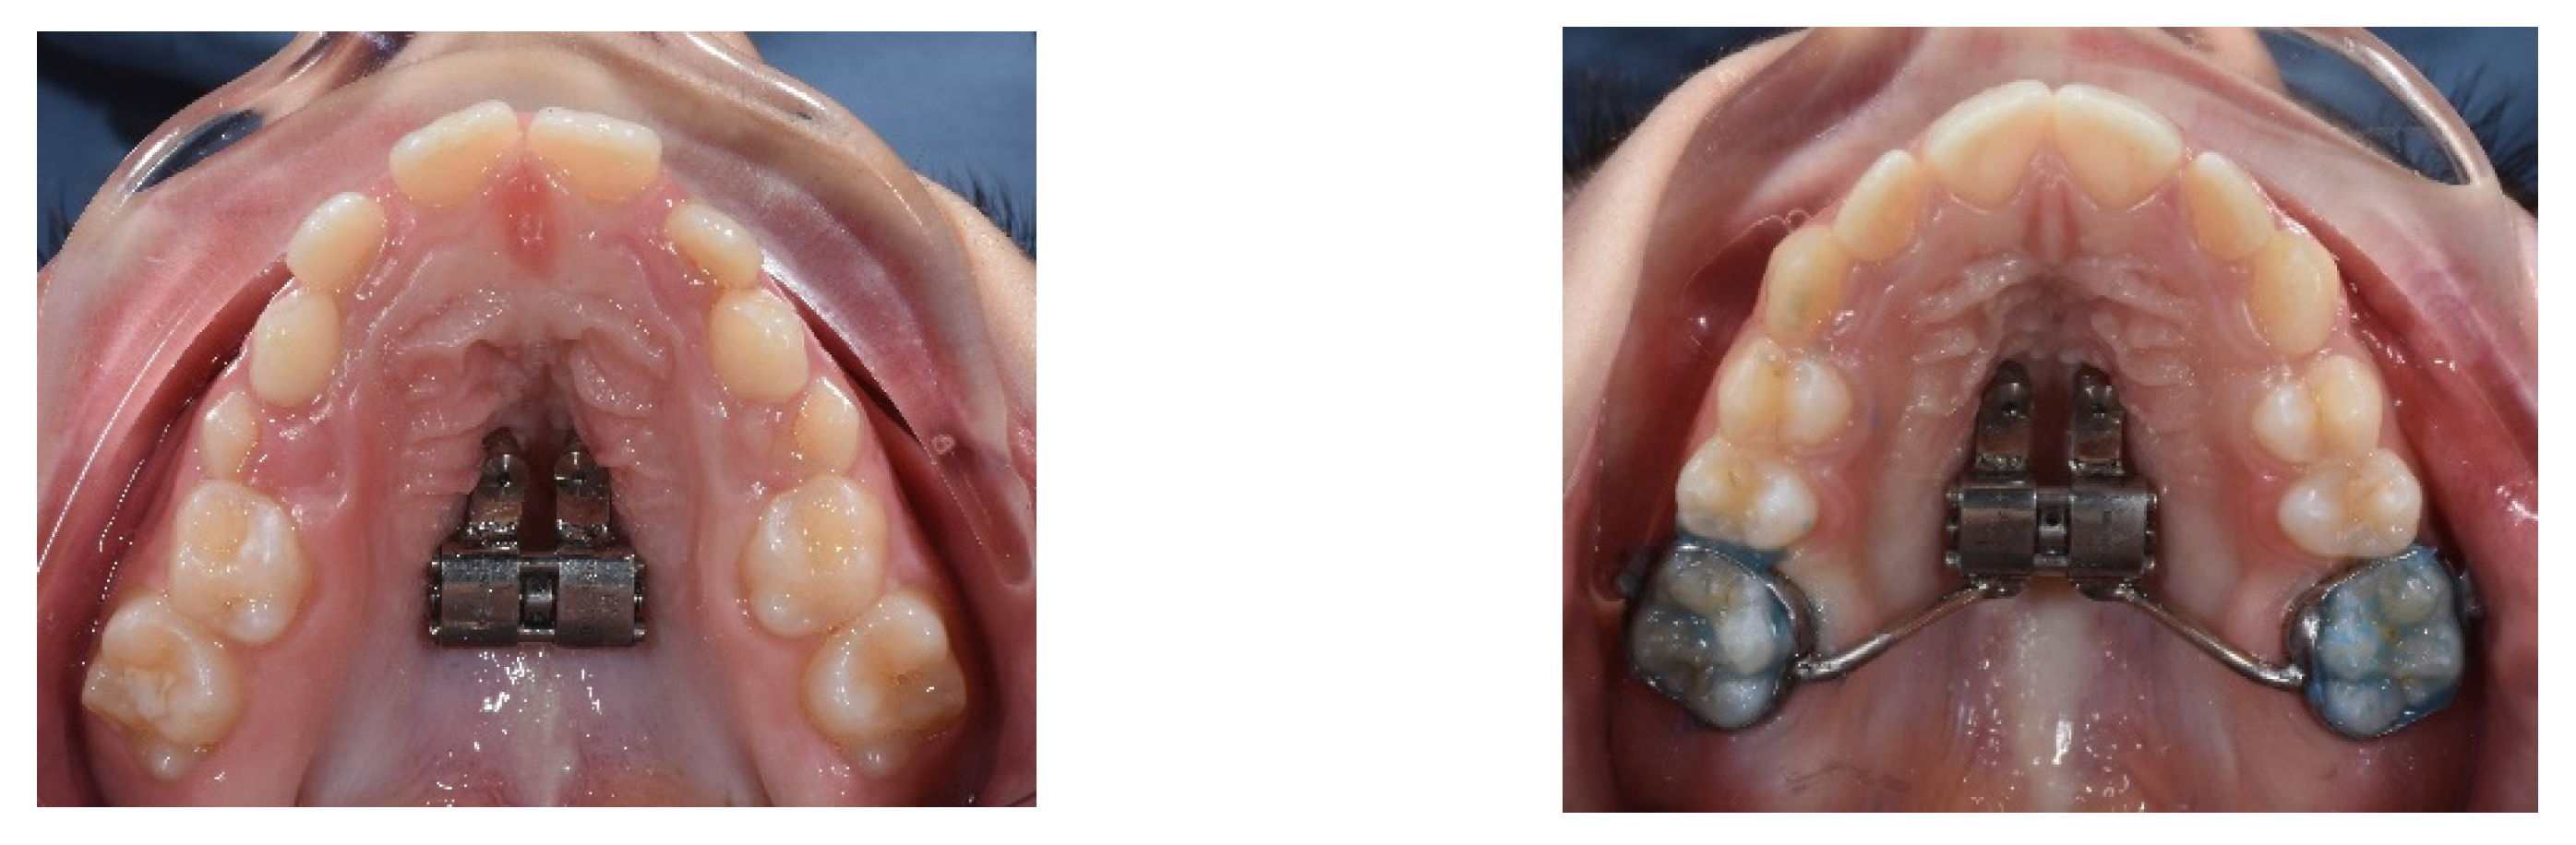

4. Case Report

4.3. Treatment Strategy

4.4. Treatment Progress